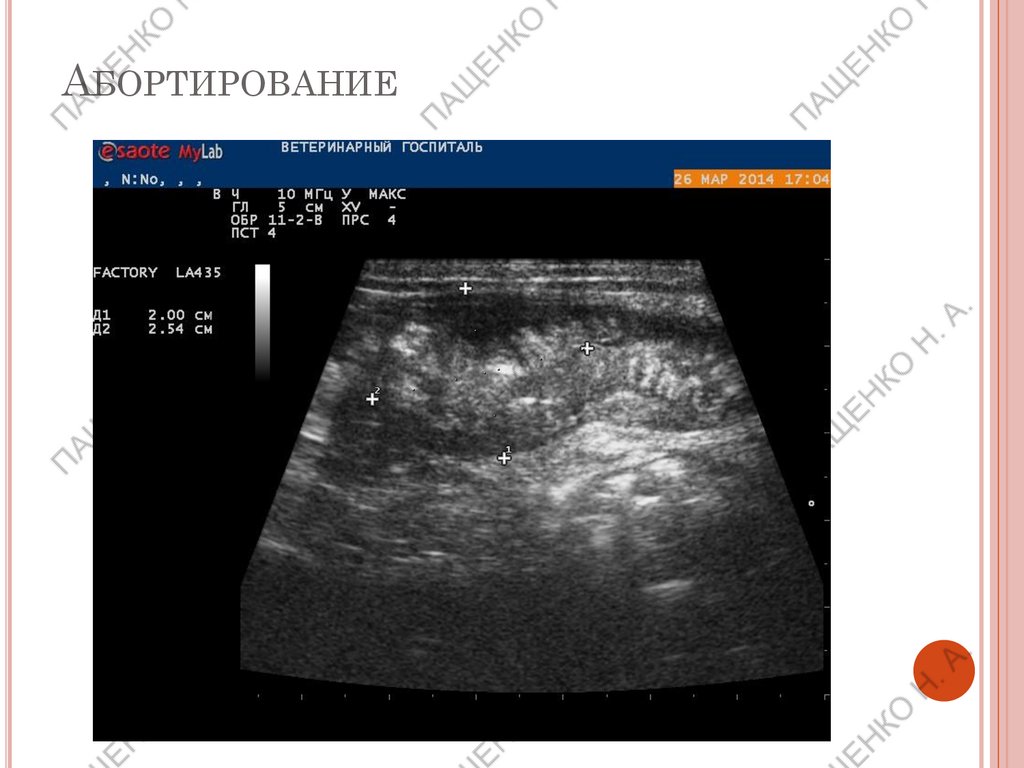

АБОРТИРОВАНИЕ

ПАТОЛОГИЯ БЕРЕМЕННОСТИ

Резорбция плодов (как правило ранние сроки, до

42 дня без вреда для животного)

Абортирование (как правило поздние сроки)

Мертвые плоды (нет движения, сердцебиения),

частичная гибель плодов (длина погибшего м.б.

плода меньше живого, если произошла

мумификация).